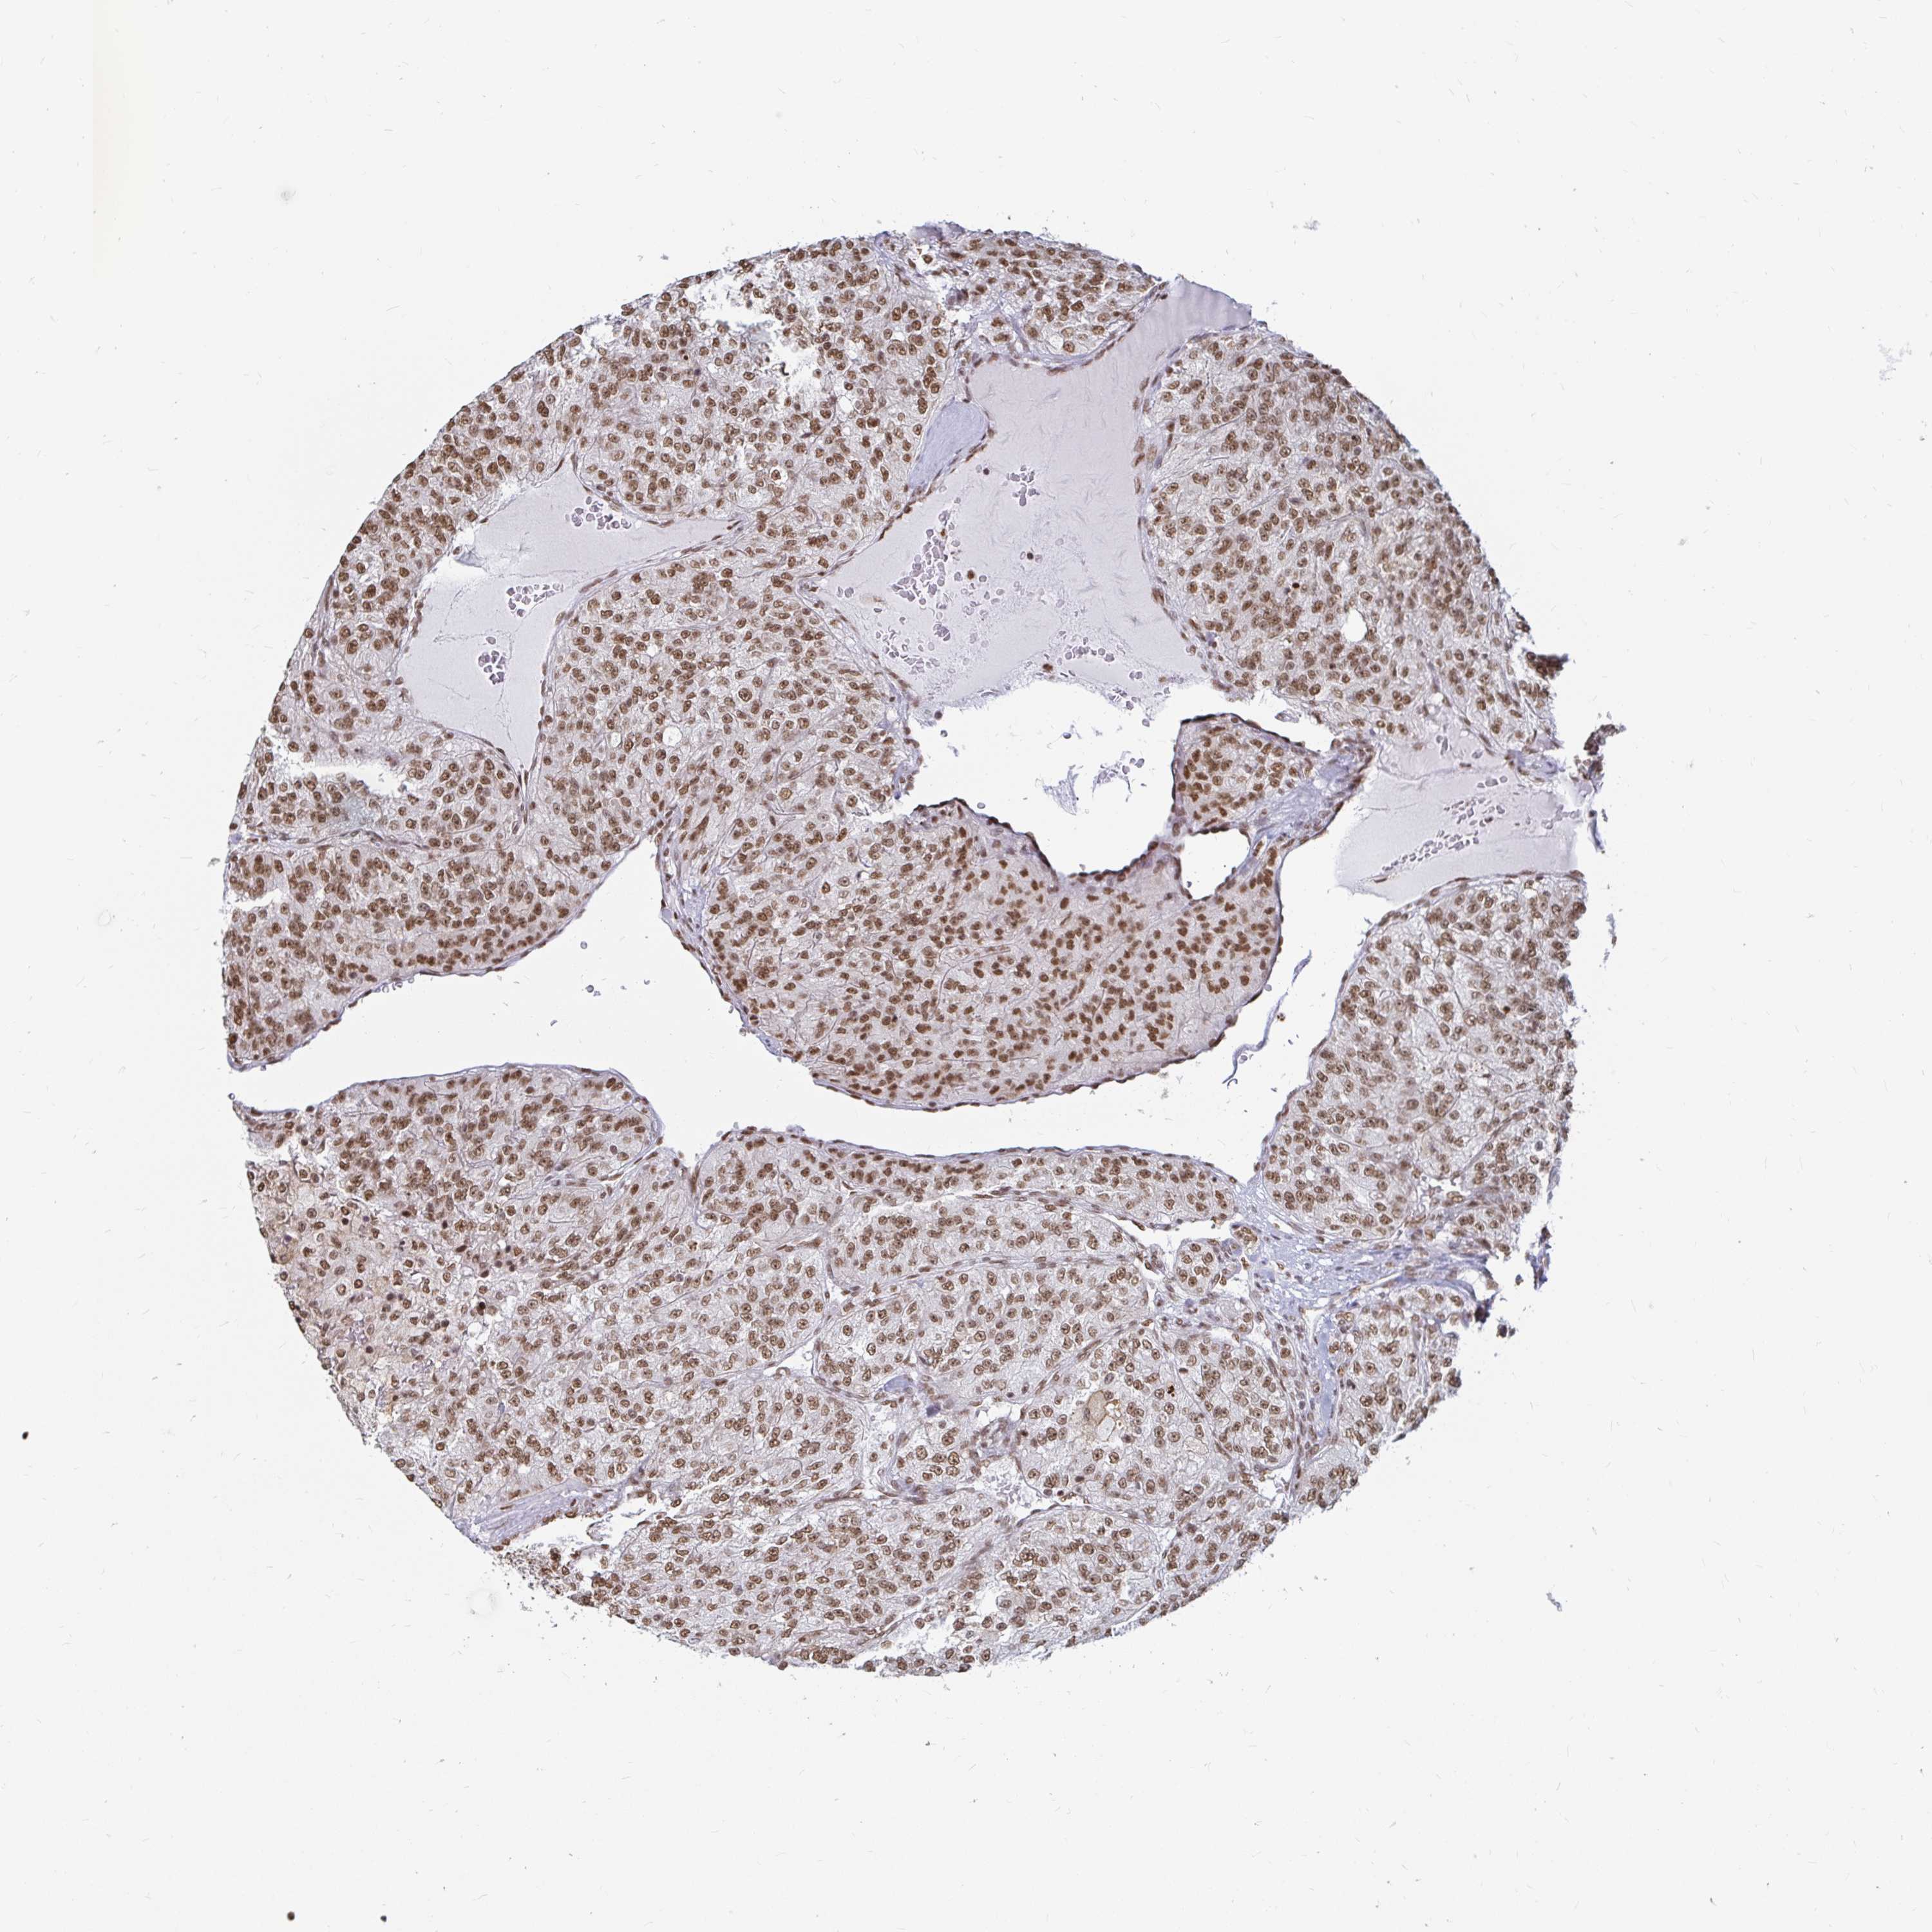

KIDNEY RENAL PAPILLARY CELL CARCINOMA (TCGA) - Interactive survival scatter ploti

The Survival Scatter plot shows the clinical status (i.e. dead or alive) for all individuals in the patient cohort, based on the same data that underlies the corresponding Kaplan-Meier plots. Patients that are alive at last time for follow-up are shown in blue and patients who have died during the study are shown in red.

The x-axis shows the expression levels (FPKM) of the investigated gene in the tumor tissue at the time of diagnosis. The y-axis shows the follow-up time after diagnosis (years). Both axes are complimented with kernel density curves demonstrating the data density over the axes. The top density plot shows the expression levels (FPKM) distribution among dead (red) and alive patients (blue). The right density plot shows the data density of the survived years of dead patients with high and low expression levels respectively, stratified using the cutoff indicated by the vertical dashed line through the Survival Scatter plot. This cutoff is automatically defined based on the FPKM cutoff that minimizes the p-score. The cutoff can be changed by dragging the vertical line or by entering a cutoff value in the square labeled "Current cut-off".

Under the Survival Scatter plot the p-score landscape (black curve; left axis) is shown together with dead median separation (red curve; right axis). Dead median separation is the difference in median mRNA expression between patients who have died with high and low expression, respectively. It is calculated as follows: median FPKM expression of dead patients with high expression - median FPKM expression of dead patients with low expression. This is intended to aid the user in visually exploring custom cutoffs and the associated p-scores and dead median separation.

Individual patient data is displayed and can be filtered by clicking on one or more of the category buttons on the top of the page. Categories describing expression level and patient information include: high, low, alive, dead, female, male and tumor stages. The scale of the x-axis can be toggled between linear and log-scale by clicking on the "x log" button. Mouse-over function shows TCGA ID, patient information and mRNA expression (FPKM) for each patient.

& Survival analysisi